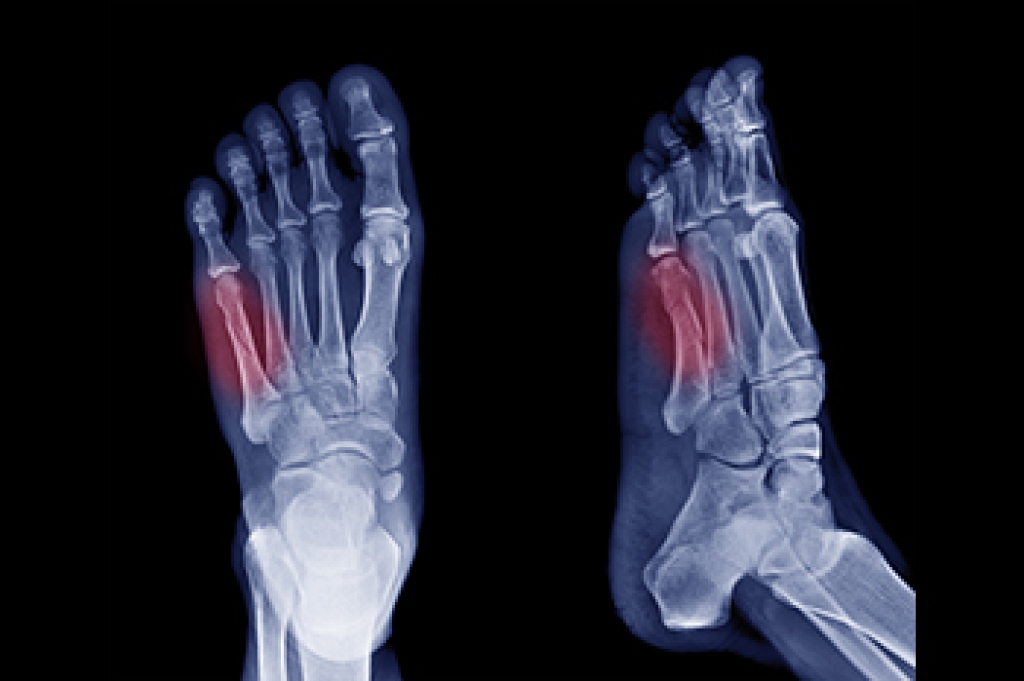

- Check to see if they have Clubfoot (condition that affects your child’s foot and ankle, twisting the heel and toes inward) which is one of the most common nonmajor birth defects.